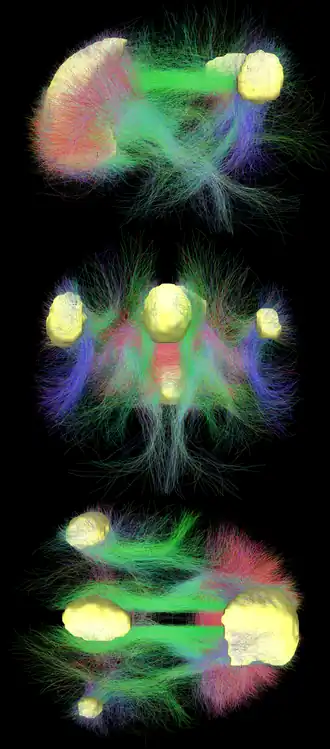

A ressonância magnética de difusão mostra tratos de substância branca que conectam diferentes áreas da DMN.[17] As conexões estruturais encontradas na ressonância magnética por difusão e as correlações funcionais da fMRI de estado de repouso mostram o maior nível de sobreposição e concordância nas áreas da DMN.[1] Isso fornece evidências de que os neurônios nas regiões da DMN estão ligados entre si por meio de grandes extensões de axônios e isso faz com que a atividade nessas áreas se correlacione.